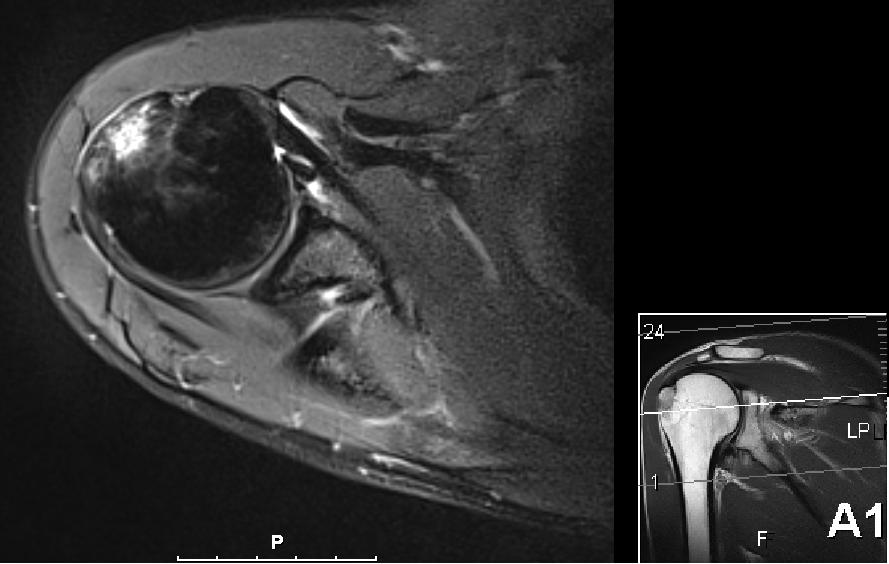

I forrige uke kom uansett svaret og resultatet var ikke akkurat helt som forventet. Nå var det riktig nok noe betennelse (aka bursitt) i skuldra som forventet men det var også et brudd i kanten på skuldra, såkalt tuberculum majos fracture på 2 x 2 cm. Så Kristian og Jørn Erik var rimelig overrasket over at jeg meldt tilbake at svømmingen gikk så bra.

Nå er det bare 6 dager til Ironman 70.3 Mallorca, og som alltid så ønsker jeg selvsagt å delta, men forstår at det kanskje ikke er det mest fornuftige. Om noen av dere har erfaringer eller gode råd/tips så tas de i mot med stor takk! Nå forstår jeg at radiolog er et eget yrke og tolking av MR-bilder krever mye erfaring og kunnskap, men jeg syntes ikke det ser såååå ille ut egentlig.

Skulderbilde

Allan - Skulder ovenfra 2

Allan - Skulder ovenfra 3